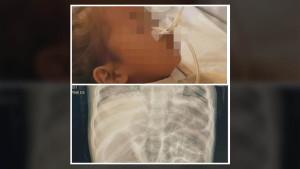

TRIBUNNEWS.COM, JAKARTA - Berikut sosok Ketua Umum Ikatan Dokter Anak Indonesia (IDAI), dr Piprim Basarah Yanuarso mulai Jumat (22/8/2025), tak lagi diperkenankan menangani pasien anak dengan cover BPJS Kesehatan di Rumah Sakit Cipto Mangunkusumo (RSCM) Jakarta.

Pada sebuah video yang diunggah melalui akun Instagram pribadinya, dr Pirim menjelaskan keputusan tersebut merupakan arahan dari Direksi RSCM dan Kementerian Kesehatan.

Dokter spesialis jantung anak itu, menjelaskan pasien harus membayar mandiri dengan biaya minimal sekitar Rp 4 juta untuk pemeriksaan echo jantung.

"Kepada seluruh orang tua pasien saya, anak-anak dengan penyakit jantung bawaan maupun didapat, mohon maaf sebesar-besarnya. Bahwa mulai hari ini saya tidak bisa lagi melayani putra-putri bapak ibu yang menggunakan BPJS di PJT atau di Kiara RSCM. Atas arahan Direksi RSCM maka saya hanya bisa melayani pasien di Poli Swasta Kencana RSCM," kata dr Piprim melalui akun Instagram pribadinya, Jumat (22/8/2025).

Menurutnya, untuk pemeriksaan echo kini pasien harus membayar sendiri karena tidak ditanggung BPJS.

"Sehingga untuk bisa berobat dan diperiksa echo sekarang Bapak Ibu harus membayar sekitar Rp 4 juta rupiah karena di sana tidak dicover BPJS," ujarnya.